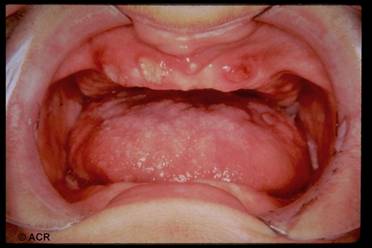

Sindrome di Behcet

È una malattia cronica multisistemica che colpisce prevalentemente soggetti giovani di sesso maschile. È caratterizzata dalla triade: uveite, ulcere oro-genitali e artralgie. È più frequente in Giappone ed in Turchia ed è associata con l'HLA-B5, con il B12 per quanto riguarda le lesioni cutanee e DR7 per quanto attiene il coinvolgimento oculare.

1) Ulcere:

Orali (lingua, palato, guance e gengive) e genitali (nell'uomo a livello scrotale, nella donne a livello delle grandi labbra e delle pareti uterine);

Hanno un diametro massimo di

Hanno colorito grigio - giallastro e sono circondate da un alone eritematoso;

Regrediscono spontaneamente, senza reliquati, nello spazio di qualche settimana, per ripresentarsi a distanza di settimane, mesi o anni.

Criteri diagnostici

Ulcere ricorrenti del cavo orale più due manifestazioni tra le seguenti:

Ulcere genitali ricorrenti;

Lesioni oculari;

Lesioni cutanee;

Pathergy test positivo